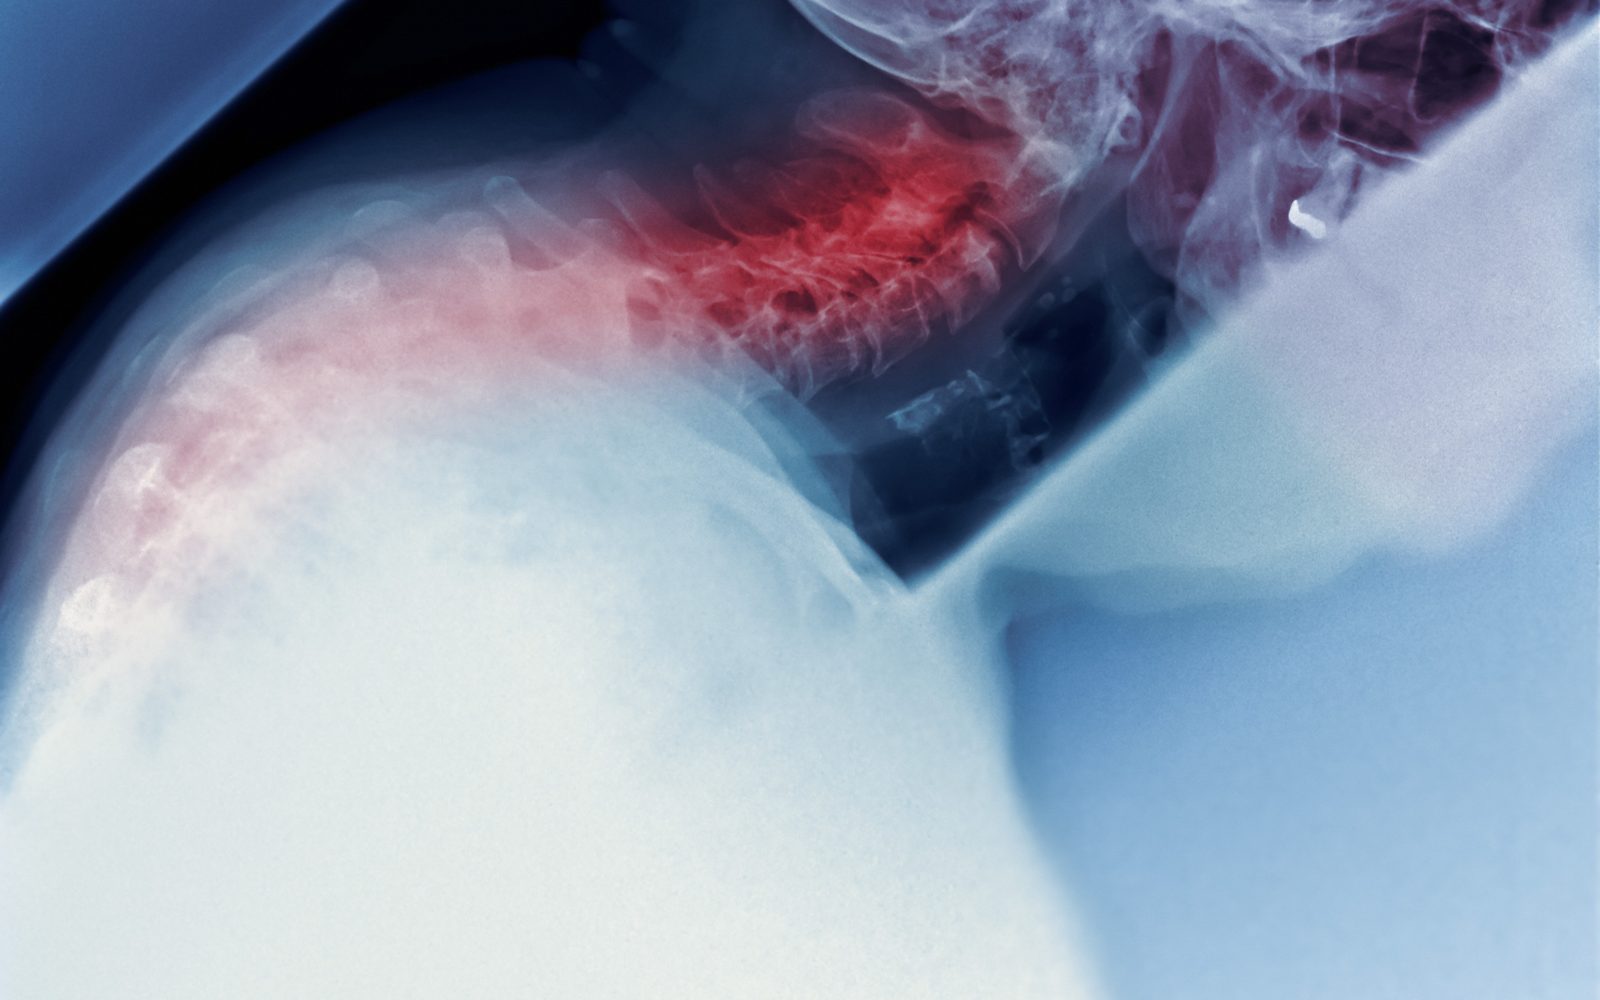

Ob dolgotrajni nepravilni drži se vezi in mišice, ki držijo hrbtenico pokonci, raztegnejo in popustijo, hrbtenica pa se začne ukrivljati.

Nastane kifoza – stanje, pri katerem se razvije značilna grba, ki pa ni le estetska težava. Spremljajo jo tudi kronične bolečine v vratu, ramenih in hrbtu.

Huda ukrivljenost hrbtenice naprej ali hiperkifoza pa je povezana tudi z zmanjšano hitrostjo hoje, slabim ravnotežjem in višjim tveganjem za umrljivost, obenem pa negativno vpliva tudi na samozavest, prebavo, gibanje in dihanje.